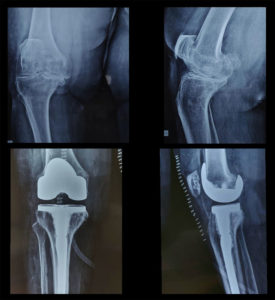

History: 76-year-old female with gross deformity in her right knee.

Treatment: Opting for an ‘extension stem’ procedure is always advisable for obese osteoporotic patients; Dr. Amyn Rajani performed exactly the same on this particular patient. While it adds to the cost, it prevents periprosthetic fractures, which could lead to surgical complications as well as financial ramifications in the future.